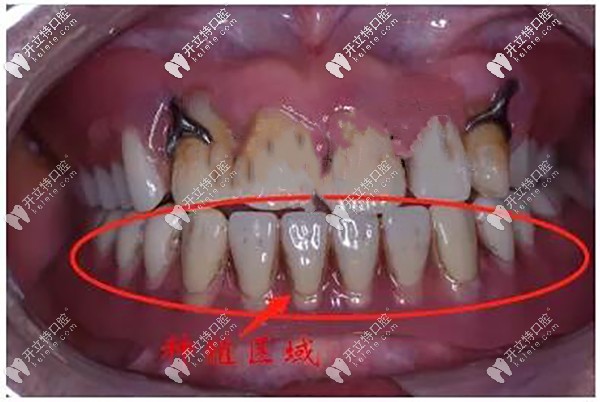

先給老人把口腔內(nèi)的牙齒遺 留的殘根、松動(dòng)牙齒拔除掉▼

牙齒遺 留的殘根、松動(dòng)牙齒拔除掉